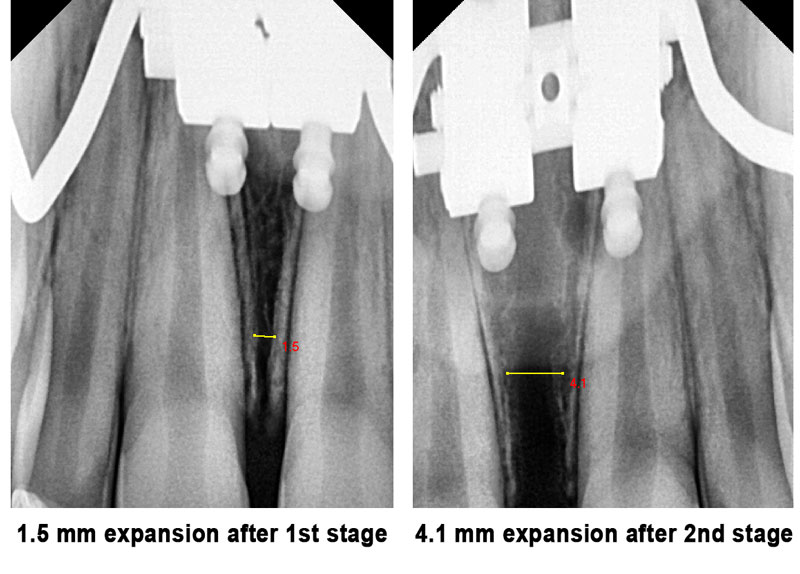

Case #6 with two-stage MSE and using only two screws

This patient was looking for an orthodontist in Houston who specialized in MSE expansion to improve her breathing while sleeping with her mouth open. She has a very narrow upper jaw, with the posterior teeth not visible while smiling.

Dr. Kanaan made her a custom-made MSE using only a 2-screw narrow MSE. Dr. Kanaan was not satisfied with the width after stage one and decided to do a second stage to get further expansion and enhance her breathing. The final results were magnificent, and the patient was extremely pleased with her functional, breathing, and cosmetic results.

Notice the above sequence of changes in her upper jaw width. The X-rays below also show her expansion and suture opening after stage one and after stage two.